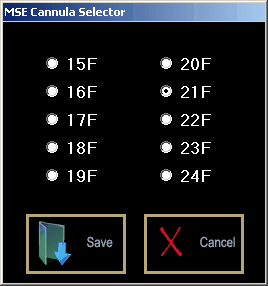

Clicking the <Select Return Cannula> button opens up the Cannula Selector window.

Return Cannula Selector Interface:

Select the cannula size that you want and then click <Save> to close the window. Click <Devices><ECMO System> to return to the ECMO system itself.